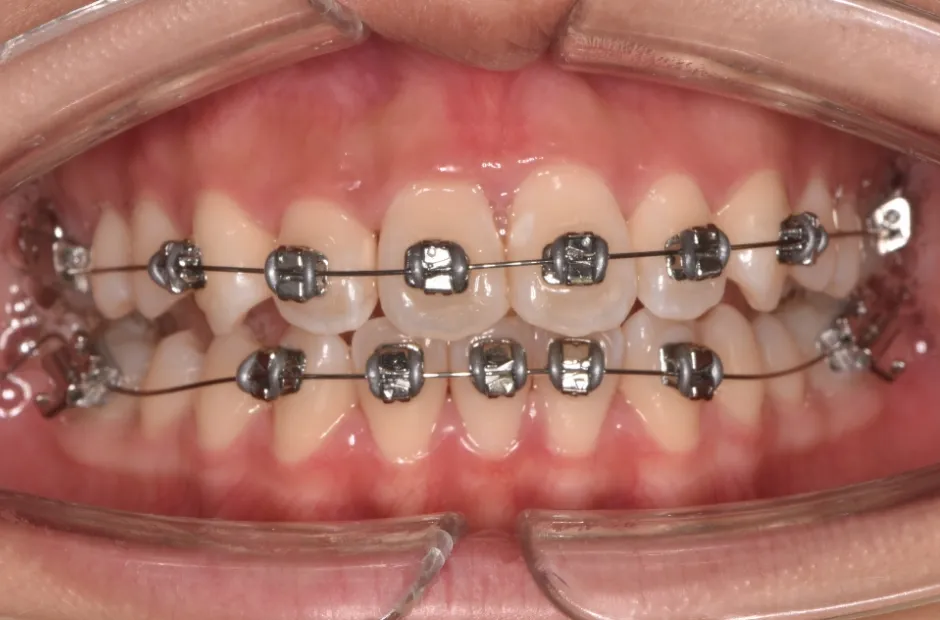

治療症例

ブラケット矯正

前歯部反対咬合

| 診断名・主訴 | 前歯部反対咬合 |

|---|---|

| 年齢・性別 | 14歳・男性 |

| 治療期間・回数 | 1年2か月 |

| 治療に用いた主な装置 | ブラケット矯正 |

| 抜歯部位 | なし |

| 治療費 | 60万円(税抜) |

| リスク・副作用 | 装置による違和感・疼痛・歯肉退縮・歯根吸収・虫歯のリスクなど |

治療中